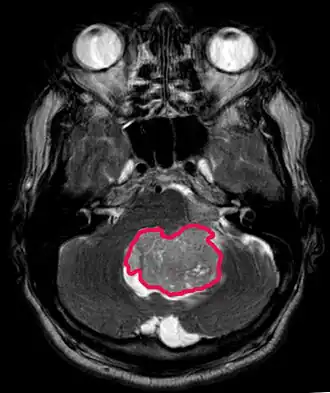

Medulloblastomen

Medulloblastoom is de meest voorkomende kwaadaardige hersentumor bij kinderen. De hoogste incidentie komt voor bij kinderen in de leeftijd van 2 tot 7 jaar. Het grootste risico op ziekte blijft in de kindertijd, aangezien medulloblastoom zeer zeldzaam is bij mensen ouder dan 21 jaar.

Deze tumor is typerend voor de achterste fossa, waar hij is gelokaliseerd in beide hemisferen van het cerebellum of in de cerebellaire vermis. Omdat het invasief en snelgroeiend is, verspreidt het zich gewoonlijk naar andere delen van het centrale zenuwstelsel (CZS) via het CSF en kan het de bodem van het nabijgelegen vierde ventrikel en de hersenvliezen infiltreren. Meer zelden kunnen aanvullende CZS-metastasen optreden. Wanneer de maligniteit optreedt, omvatten de symptomen verlies van evenwicht, coördinatiestoornissen, diplopie, dysartrie en als gevolg van betrokkenheid van de vierde ventrikel, wat vaak resulteert in obstructieve hydrocephalus, hoofdpijn, misselijkheid en braken, en onstabiel lopen.

MRI toont meestal een enorme contrastverhogende laesie waarbij het cerebellum betrokken is. Zoals hierboven vermeld, heeft medulloblastoom een hoge neiging om lokaal de leptomeningen te infiltreren en zich ook door de subarachnoïdale ruimte te verspreiden, waarbij de ventrikels, cerebrale convexiteit en leptomeningeale oppervlakken van de wervelkolom betrokken zijn. Daarom is het noodzakelijk om de gehele craniospinale as in resonantie te brengen.

Het doel van de operatie is om zoveel mogelijk van de door de laesie gepresenteerde massa te verwijderen. In feite resulteren postoperatieve resterende tumoren in een slechtere prognose. Ook een voorbode van een ongunstige prognose is de aanwezigheid van tumorcellen in het hersenvocht of de resonantiedetectie van leptomeningeale metastasen. Een operatie alleen is meestal niet genezend. In sommige gevallen kan echter therapeutische bestraling van de craniospinale as, gericht op de primaire tumorplaats, het gevolg zijn. Het toevoegen van chemotherapie na bestralingstherapie verhoogt het genezingspercentage. Op platina gebaseerde geneesmiddelen (cisplatine of carboplatine), etoposide en een alkyleringsmiddel (cyclofosfamide of lomustine) worden samen met vincristine gebruikt. Met de juiste behandeling variëren de gevallen met een lange overleving van meer dan 3 jaar bij patiënten met medulloblastoom van 60 tot 60 jaar en 80 procent.